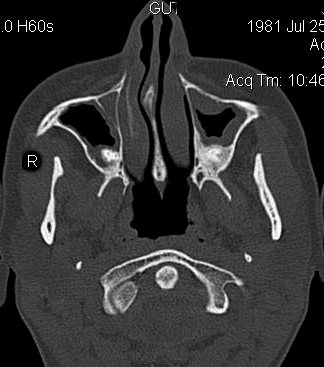

TC exostosis occipital congénica.

TC exostosis occipital congénita.